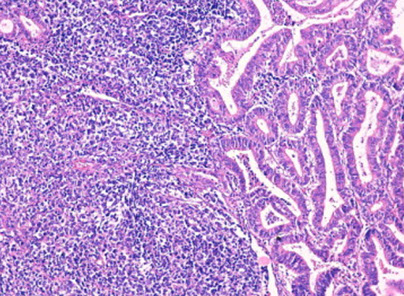

High-grade Neuroendocrine Carcinoma (HG-NEC)

Rare (more common in cervix); Small or large cell type; various architectures (occasionally has rosette-like structures), usually assoc c em-oid AC

- small cell type has round or spindly cells c min-mod cytoplasm, uniform nuclei w/wo nucleoli

- large cell has lots of cytoplasm c variable-sized vesicular or hyperchromatic nuclei, occasional nucleoli, prominent mits, geographic necrosis, neuro-vascular invasion

- IHC: + CK, EMA, CAM5.2, CD56, SYN, S100, p16

- px aggressive (<1 yr survival)